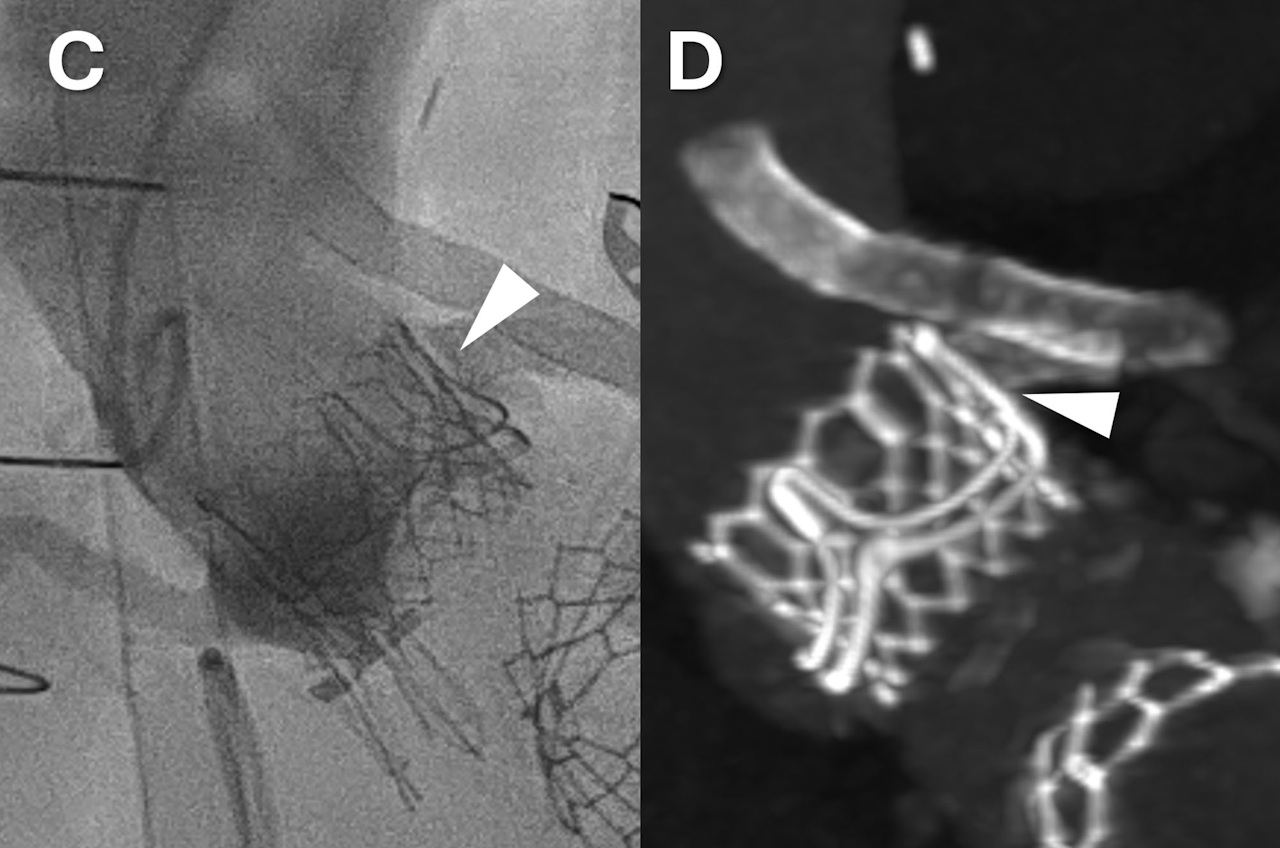

Новий аортальний клапан пацієнта одразу після введення в судину (зліва) та наступного дня (справа). Білим трикутником показане місце, де він перекриває старий зв'язок між аортою й коронарною артерією, щоб кров текла крізь шунт. Bruce et al. / Circulation: Cardiovascular Interventions, 2026

Натомість лікарі провели операцію за протоколом VECTOR під загальною анестезією. Пацієнту в стегнові вену й артерію ввели катетери, крізь які проводили подальші маніпуляції. Усі крихітні інструменти для операції рухалися всередині тіла чоловіка під впливом електричного струму. Коли вони досягли оболонки серця, перикарду, лікарі з’єднали ліву гілку аорти з лівою коронарною артерією. Коли ж лікарі підтвердили, що у пацієнта стабільний кровообіг, вони замінили старий клапан аорти на новий, який також ввели через катетер. За пів року після операції чоловік залишався здоровим, приймаючи ліки від надмірного згортання крові.